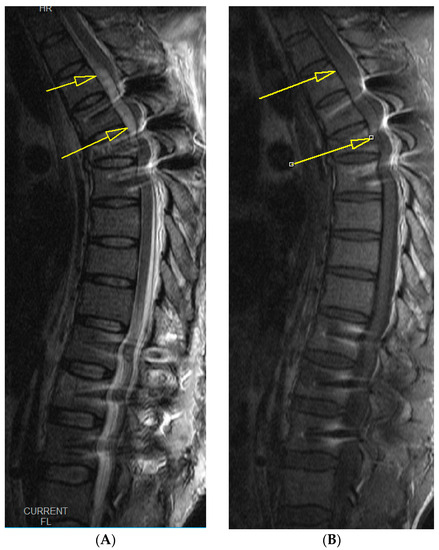

2. Case Report